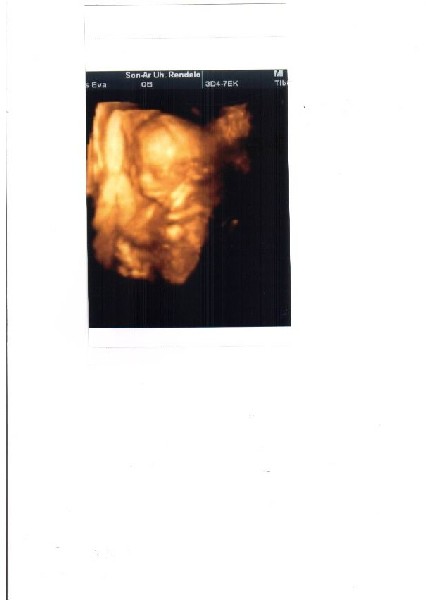

Enyém gyerek is egyre határozottabb olyannyira hogy egyfolytába piszkál,ütvág,nagyon eleven

afp:0,72

hcg:1.28

ue3 0,91

18as triszomára esély:1:10000

velőcsőrendellenességre:1:10000

21es triszómára :1:931hez

fals eredményre5 %

mindhárom szűrés eredménye negatív.Tied milyen?

afp eredméynemet fentebb leírtam,nem tudom visszaolvastad e ez a 4ik afpém

de ez most jó lett úgyhogy remélem minden oké.Egyébként nekem a 2ik babóm lesz,de ez nem számít akkor is nézik,mindenkinek.De hogy minek?

ez aza afp több mint jó,szerintem megnyugodhatsz

hát ezek az uhák már csak ilyenek,érdekes engem a szar véreredméynnel se néztek tovább 5 percnél,végtagok rendben,nyaka,feje,szíve,gyomra,hólyag azt ennyi szevasz.